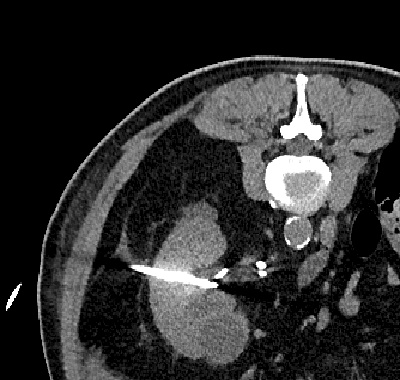

CT-gesteuerte perkutane Nephrostomaanlage bei einem einnierigen Patienten mit drohendem postrenalen Nierenversagen